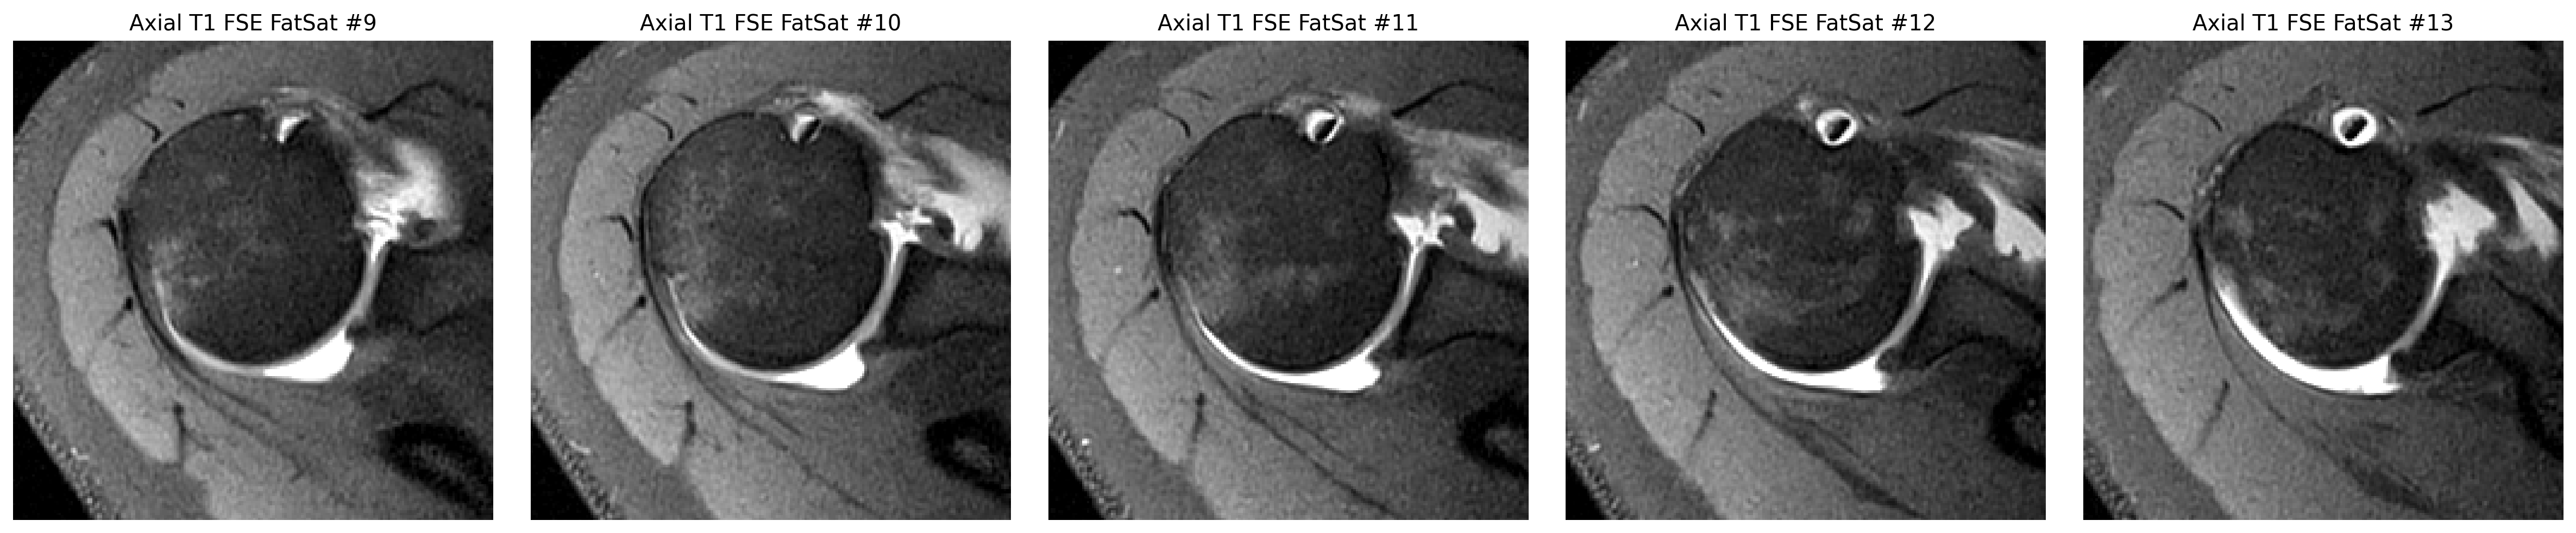

The cuff finding was checked in coronal and sagittal views, while the labrum was reviewed on axial arthrogram slices.

The strongest image-only read is a smaller tear or split on the joint-facing side of the supraspinatus tendon where it attaches to bone.